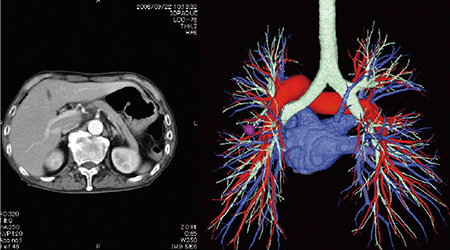

電子的な方法により,病院は診療所にCT・MRIなどの高度医療機器の検査結果画像や読影レポート(図1)などを閲覧可能な形式で送信することができます。

さらに,診療所は,病院に診療所で撮影されたデジタルX線,内視鏡,超音波などの画像を送信することができます。